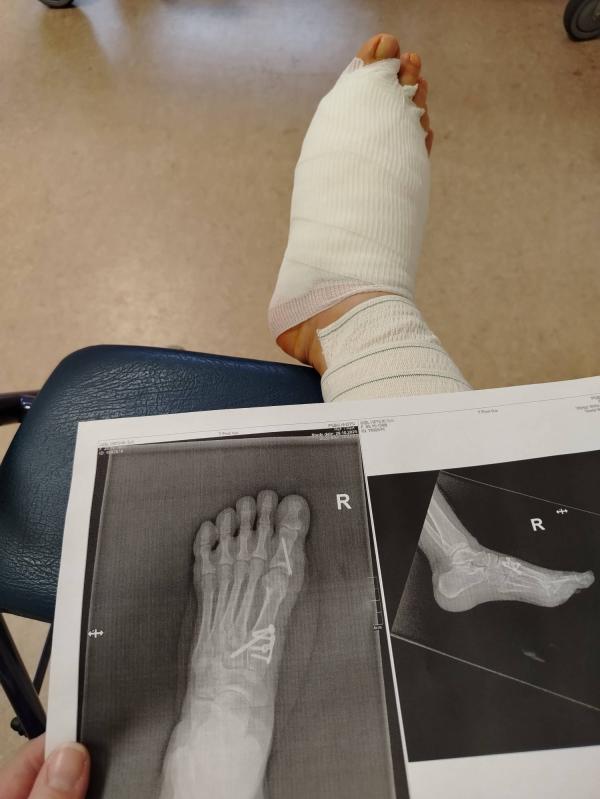

Сейчас уже всё позади, осталось прожить 3 недели на костылях, ещё три недели в туфле барука и радоваться жизни. Не мучаться с покупкой обуви. И не чувствовать боли при ходьбе.

Операция длилась час. Наркоз не общий, укол в спину + я попросила ввести меня в сон, что бы я не слышала что они там делают. На следующий день они готовы выписать домой. Но я попросилась ещё на сутки остаться, так как кружилась голова и болела нога, я думала их уколы помогут. Кормят там очень вкусно, чисто, уютно, медперсонал очень вежливый. Операция по квоте.